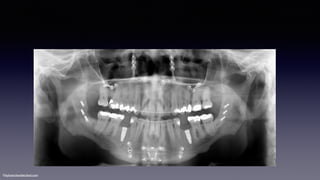

•Prior to surgery

•Root parallelism is fair

•33 & 35 are erupted

•#47 is uprighted

183 weeks